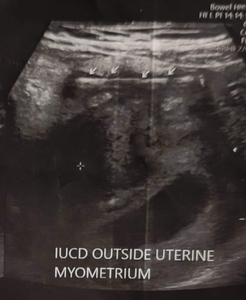

Examination revealed stable vitals, a soft, non-tender abdomen, and a normal vaginal exam. Ultrasound revealed an 8-week singleton pregnancy, with the IUCD abutting the anterior uterine wall, sigmoid adhesions, and omental wrapping. [Fig 1]